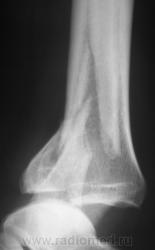

Травма. Перелом. Произведена рентгенография в стандартных проекциях в ургентном порядке.

Внутрисуставной перелом заднего края дист.эпиметафиза б/б кости или перелом "третьей лодыжки", со смещением фрагмента по ширине кзади,по длине - кверху до 5 мм и под углом, открытым кзади, с подвывихом стопы кзади, оскольчатый перелом н/3 диафиза м/б кости со смещением дистального фрагмента по ширине, по длине и угловым /открытым кзади/.

ну и еще перелом внутренней лодыжки